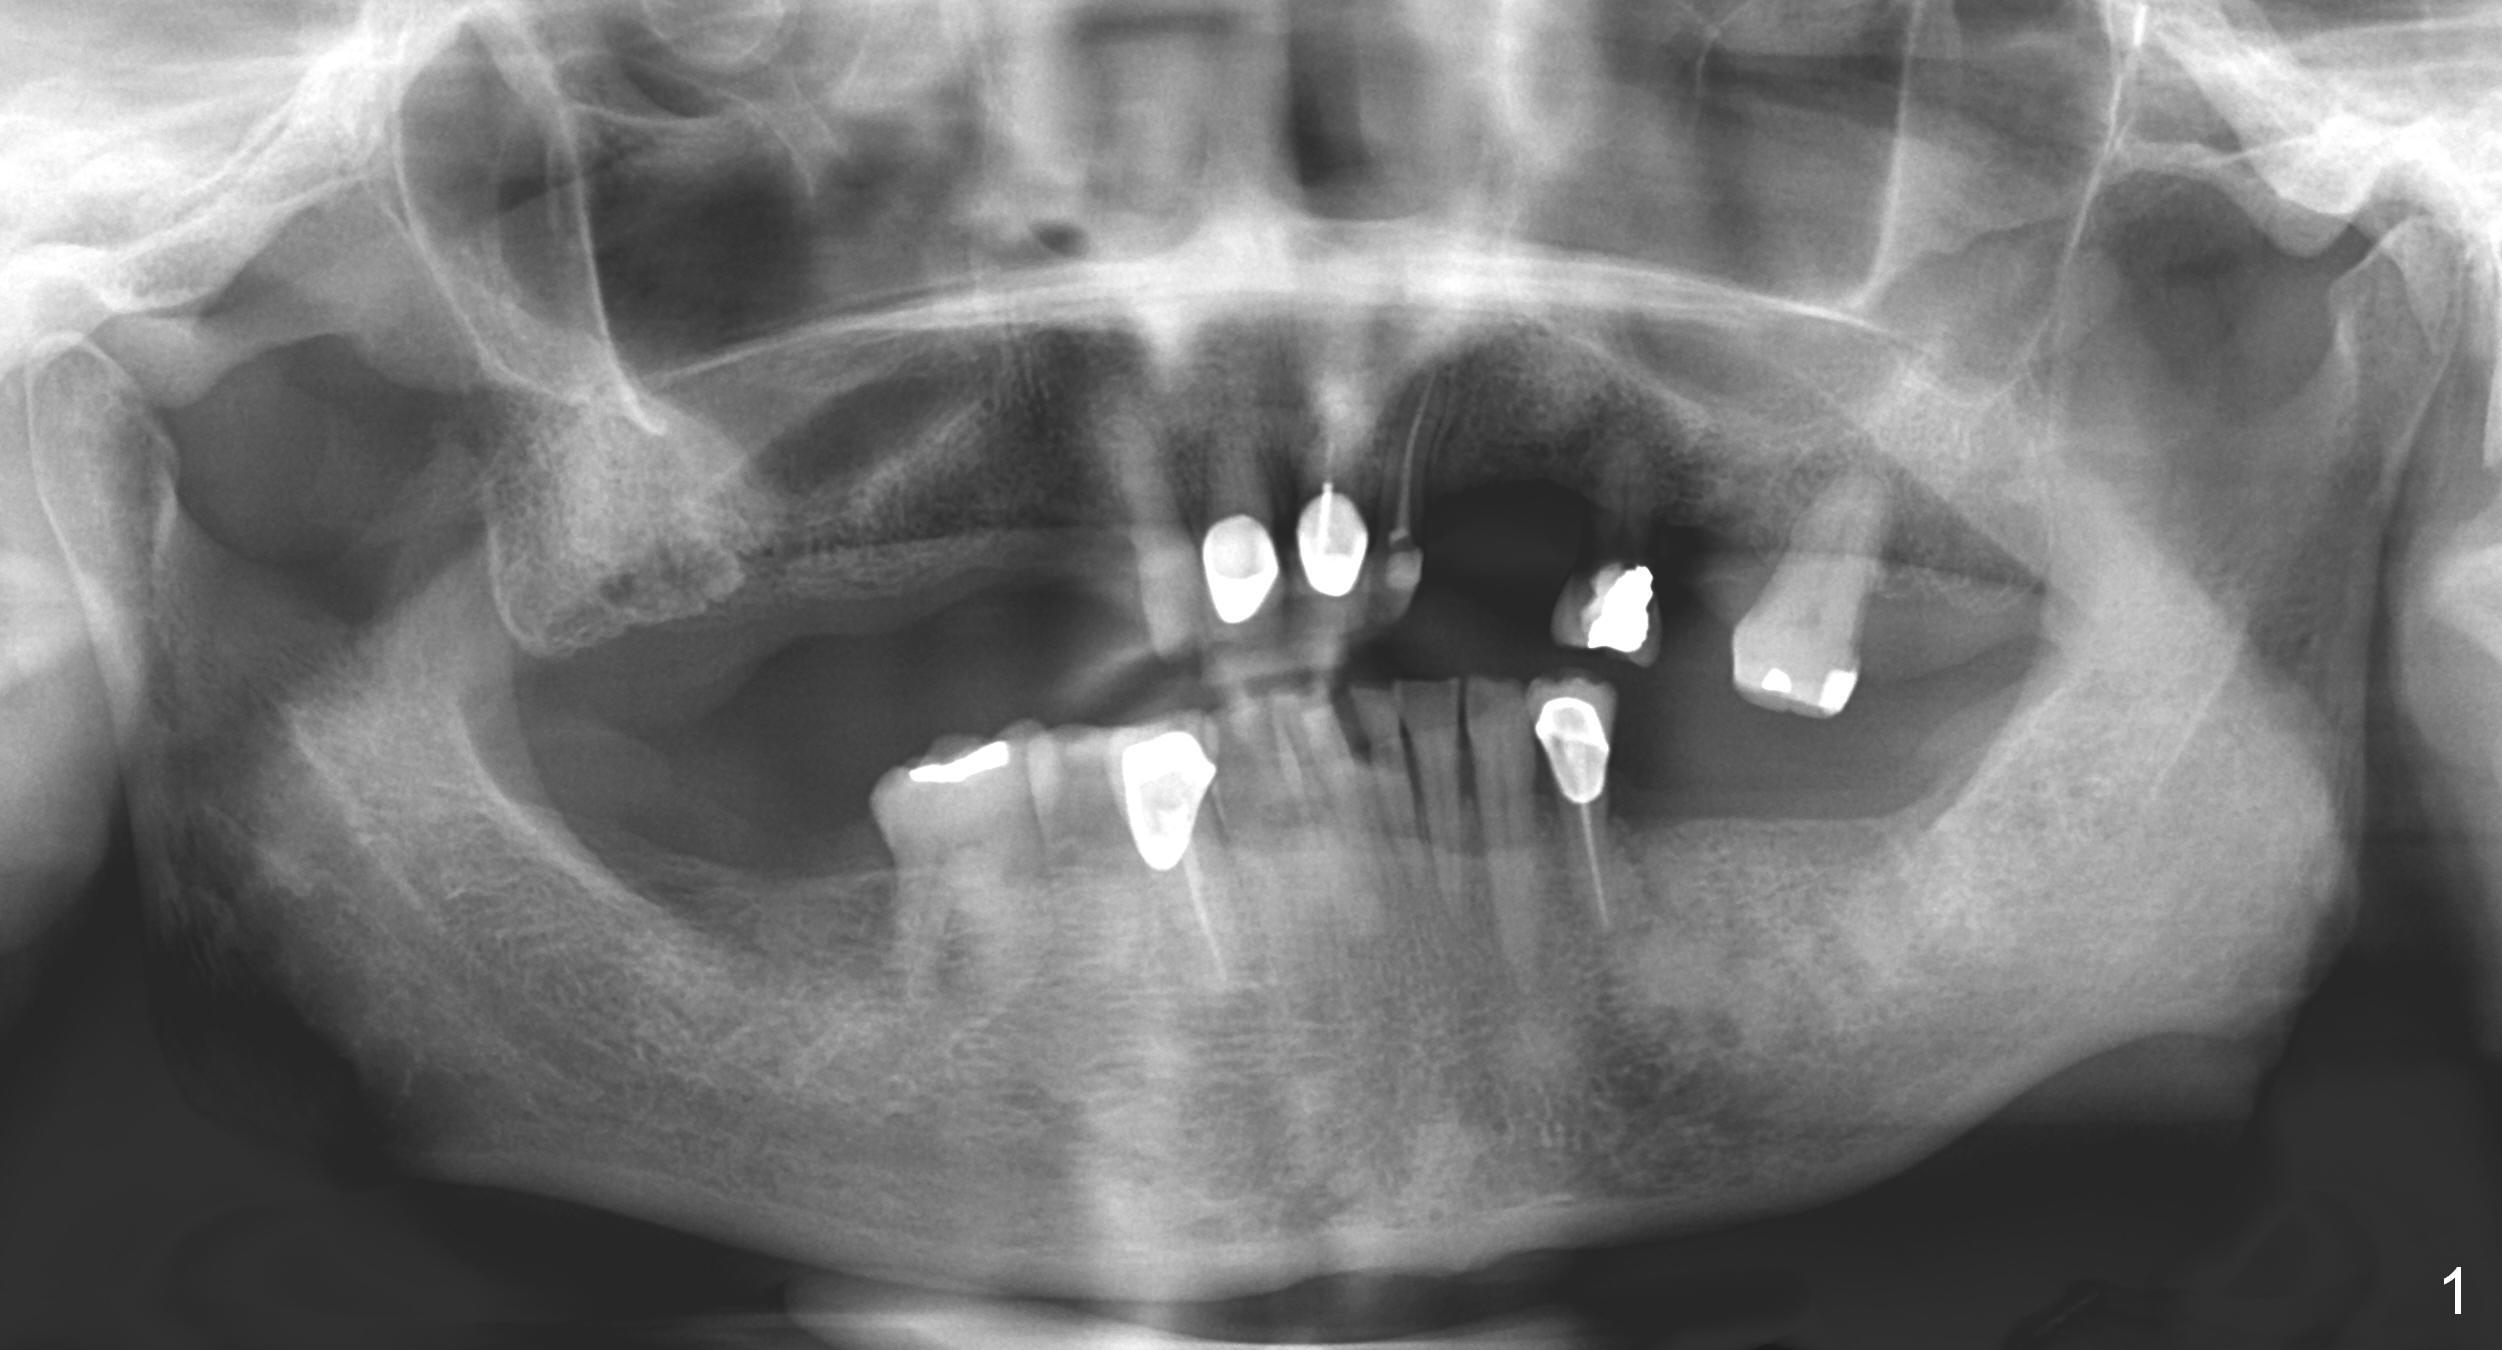

Restudy of the diagnostic wax up (Fig.4) reveals that the edentulous space at #14 is narrow mesiodistally. The pontic at #19 should be correspondingly narrow. Therefore the crown at #18 should be large (Fig.5 red outline). The initial entry point for #18 implant (Fig.6 (occlusal view of a surgical stent) *) should be immediately distal to #19.